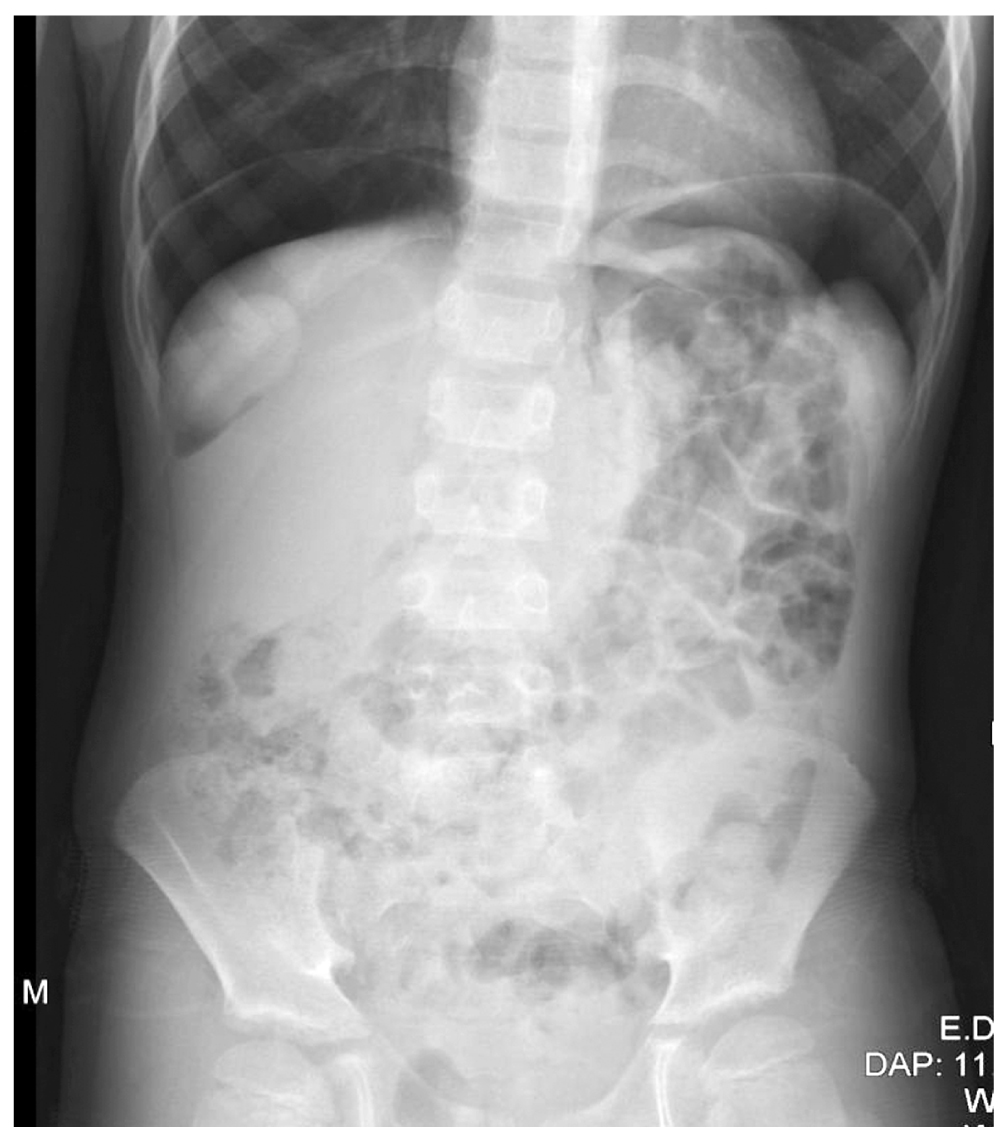

При пальпации живот мягкий, умеренно болезненный во всех отделах, симптомы раздражения брюшины (Щёткина–Блюмберга, Раздольского) отрицательные. Температура тела не повышалась. Физиологические отправления без особенностей. Клинический анализ крови, мочи, кислотно-щелочное состояние крови — в пределах возрастной нормы. Выполнена ОР ОБП, по данным которой имелись признаки свободного газа в брюшной полости, что могло указывать на перфорацию полого органа (рис. 1).

Рис. 1. Клинический случай № 1: обзорная рентгенограмма органов брюшной полости.

Fig. 1. Clinical case 1. Overview radiography of the abdominal organs.